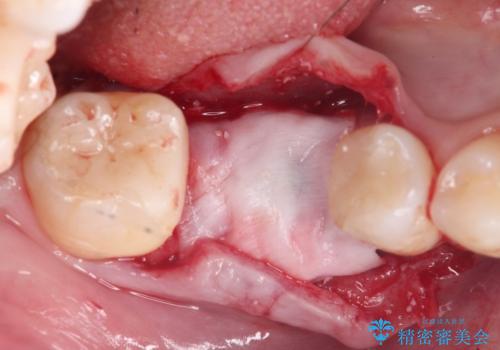

安定し、長く使用できるようなインプラント治療を実践するため、骨の増成をインプラント埋入と同時に行いました。